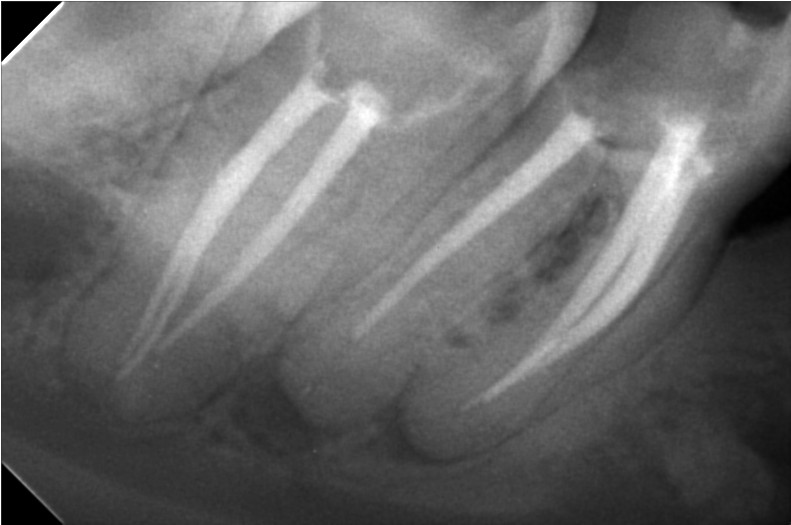

علاج الجذور يعد فرع من فروع طب الأسنان الذي يعمل على معالجة مشكلات الجذور التي تساعد على توفير الحماية والتغذية داخل الأسنان من التعرض لأي عوامل خارجية مثل: الأطعمة الساخنة والباردة هناك العديد من التقنيات التي ساعدت في علاج الجذور و التي توفرها مركز أوبال للأسنان, ومنها:جهاز الاشعة الثلاثية الابعاد , جهاز الميكروسكوب, أدوات تنظيف القنوات العصبية واخيرا حشو القنوات العصبية فكل منها لها دور مهم في عملية علاج الجذور فالاشعة الثلاثية الأبعاد تساعد في رسم خريطة دقيقة للقنوات العصبية أما الميكروسكوب فهو يعمل على توضيح الرؤية, تتيح أدوات تنظيف القنوات العصبية لأول مرة التعامل مع القنوات الضيقة والملتوية بشدة وتعد حشو القنوات العصبية عن طريق الحقن من أحدث التقنيات الطبية التي تضمن نجاح نجاح علاج الجذور أصعب الحالات من الجلسة الأولى فهي تعمل على إحكام غلق القنوات الأساسية وخصوصا الفرعية والتأكد من انها خالية من البكتيريا.